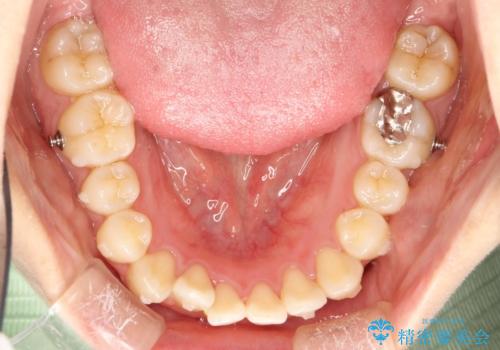

インビザラインによるガタつきの矯正治療 シンプル・短期間

- invisalign full

- 1年6ヶ月

- 非抜歯、IPR+拡大によるマウスピース矯正を計画した。